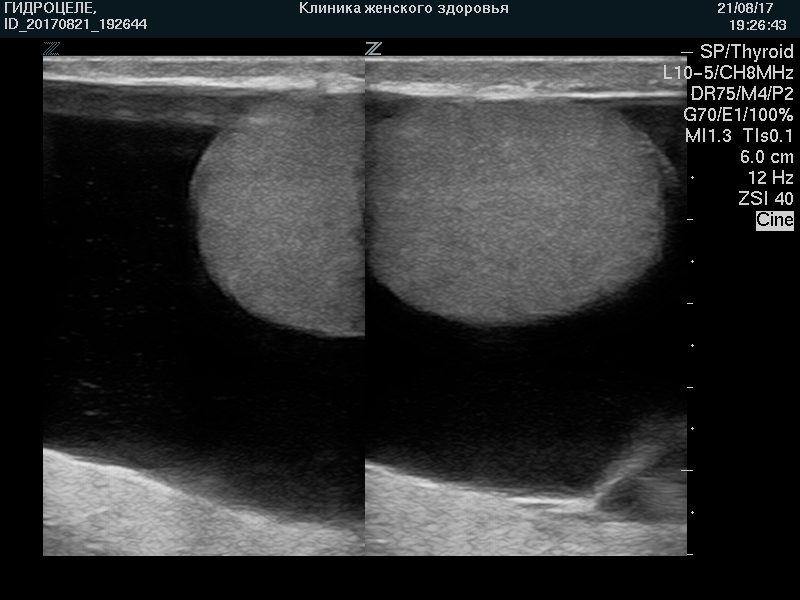

Ультразвуковая картина водянки яичка, гидроцеле, кисты придатка яичка, сперматоцеле, кисты семенного канатика, фуникулоцеле ХАРАКТЕРНА и сомнений не вызывает.

УЗИ мошонки позволяет безопасно (без «облучения») осуществлять динамический контроль на фоне лечения и/или наблюдения.

| Водянка яичка. Свободная жидкость контурирует яичко |

|

| Водянка яичка. Тот же случай. |